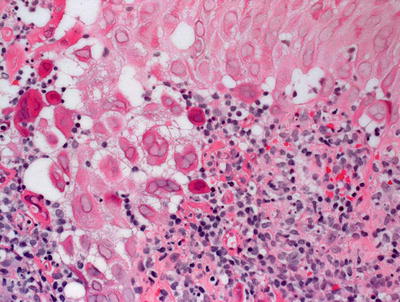

Fig. 12.9

Dissolution of the epidermis and eosinophilic cytoplasmic inclusions resembling erythrocytes are present in orf